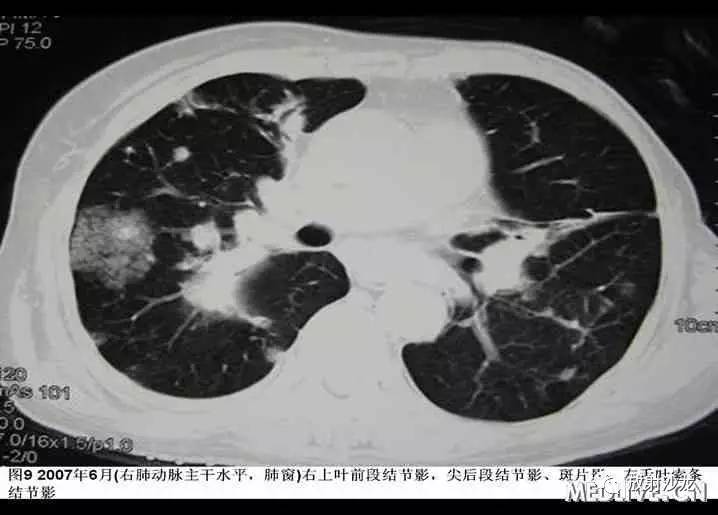

入院后患者最高体温在38℃左右,给予“拜复乐及大扶康”治疗后无显效,复查胸部CT提示肺内病变较2007年3月有加重(见图9-12),遂再次行CT引导下经皮肺穿。穿刺后患者最高体温维持在39℃左右,考虑感染不能完全除外,于2007年6月19日起加用稳可信0.5g Q8h及复达欣1.0g Q8h,6月21日加用口服大扶康200mg Qd,发热未见改善。结合两次肺穿及外院VATS的标本,病理科诊断“肺Castleman病(多中心型)(见图13)” 免疫组化:CD3(+)、CD20(+),AE1/AE3(+),CD21(+)”。6月21日转入血液科化疗,并于6月22日予CHOP方案化疗(CTX 600mg d1, 400mg d4, 西艾克4mg d1, 艾达生80mg d4, 强的松80mg d1-5)。化疗后未再发热,咳嗽、咳痰症状缓解,6月27日复查CXR示右下肺团块影较1月前吸收予以一疗程CHOP化疗后,患者体温正常,复查胸片提示右下肺阴影较前有明显吸收。后又间断予以CHOP方案化疗3程,2008年2月初,因受凉后发热,出现渐加重的气短,家属及患者放弃进一步诊疗,于2008年2月下旬去世。

本例患者的肺内病变进行性进展,不过较一般的恶性肿瘤进展要慢些。该例有发热、乏力、体重降落等全身表现,其特别之处在于其胸部影像学表现为进行性加重的双肺团块、结节影,病变部分以胸膜下分布为主,部分沿支气管血管束走行;另外,患者的肺组织病理表现为典型的CD的表现,这在既往的报道中很罕见。曾在HIV阳性的CD患者中报道过,肺影像学表现为肺实质的结节团块影。该患者既往有乳癌手术、化疗的基础,且在化疗期间患带状疱疹,说明患者的机体抵抗力很低下,这可能与其肺部的影像学特殊有一定关系。该例患者无明显自觉症状,浅表淋巴结肿大又不显著,病理学家若对此少见病缺乏认识,易漏诊。该患就是在胸腔镜活检术后1年余才明确诊断并才开始接受治疗的,这可能也是影响患者预后的重要因素。